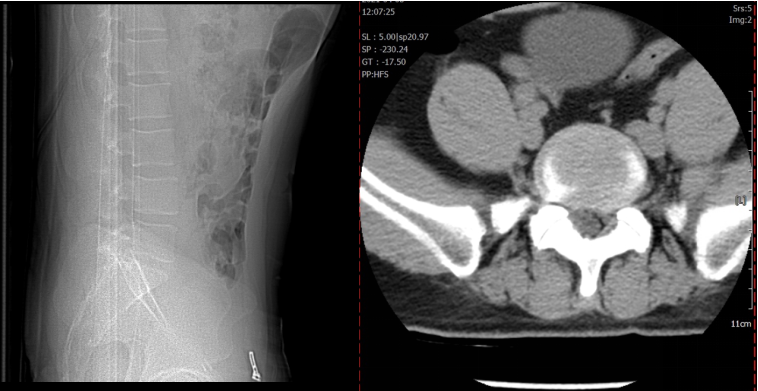

术前CT

术前MRI